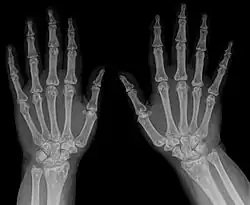

Die Osteopoikilose (auch: Osteopathia condensans disseminata, Osteopoikilie) ist eine seltene, gutartige, meist zufällig entdeckte Knochenfehlbildung. Dabei finden sich im Becken und in den Meta- und Epiphysen sowie in den Hand- und Fußwurzelknochen Cluster-artig viele, unregelmäßige, runde bis ovale Verdichtungszonen der Spongiosa von wenigen Millimetern bis Zentimetern. Die Veränderungen finden sich seltener in der Diaphyse. Oft ist das Verteilungsmuster symmetrisch. Schädel und Wirbelsäule sind selten betroffen. Die Herde gehen ohne klare Grenze in die Umgebung über. Die Kompakta ist nicht betroffen.

In einer der größten Untersuchungen zur Osteopoikilose, einer türkischen Studie von 1992,[3] fanden sich ausgehend von vier Patienten, bei denen die Osteopoikilose zufällig gefunden wurde, bei Untersuchung der Familienangehörigen schließlich 49 weitere Fälle (insgesamt 33 Männer und 20 Frauen, Verhältnis 1,65:1). Anhand der Stammbäume wurde in diesen Familien aus Ost-Anatolien und der Schwarzmeergegend eine autosomal-dominante Vererbung aufgezeigt. Bei 51 von 53 Patienten war die Osteopoikilose beidseitig. Betroffen waren vorwiegend die Metaphysen, sowie die benachbarten Knochenregionen, ohne Unterschied zwischen distalen und proximalen Metaphysen. Die Skleroseherde fanden sich in absteigender Häufigkeit in den Fingerknochen (Phalangen, 100 %), Handwurzelknochen (Carpalia, 97,4 %), Mittelhandknochen (Metacarpalia, 92,3 %), Zehenknochen (Phalangen, 87,2 %), Mittelfußknochen (Metatarsalia, 84,4 %), Fußwurzelknochen (Tarsalia, 84,6 %), gefolgt von Becken (74,4 %), Oberschenkelknochen (Femur, 74,4 %), Speiche (Radius, 66,7 %), Elle (Ulna, 66,7 %), Kreuzbein (Sacrum, 58,9 %), Oberarmknochen (Humerus, 28,2 %), Schienbein (Tibia 20,5 %) und Wadenbein (Fibula, 12,8 %).

In dieser Studie fanden sich zwischen einem und tausend Skleroseherde pro Knochen, wobei die Anzahl mit dem Alter zunahm, ebenso die Dichte (Sklerosierung). In den Beckenknochen fand sich die höchste Anzahl von Skleroseherden. Die Läsionen maßen zwischen 1 × 1 mm und 12 × 16 mm. Sie wurden als linear, elliptisch oder rund beschrieben, und waren oft entlang gedachter längsverlaufender Linien im Knochen angeordnet.